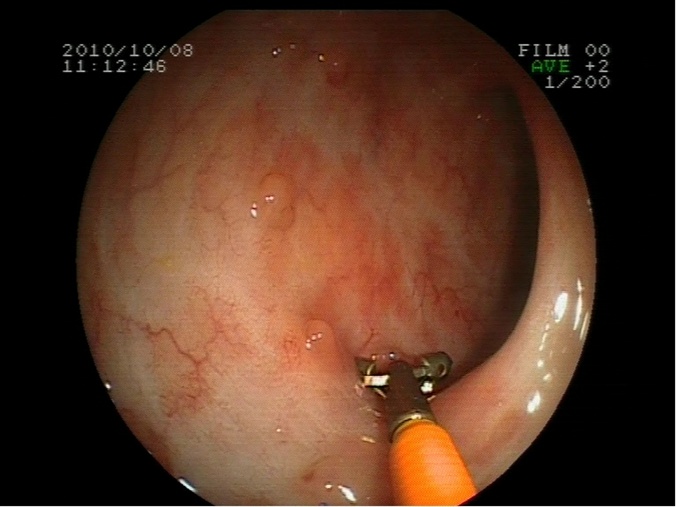

Polipectomía en ciego